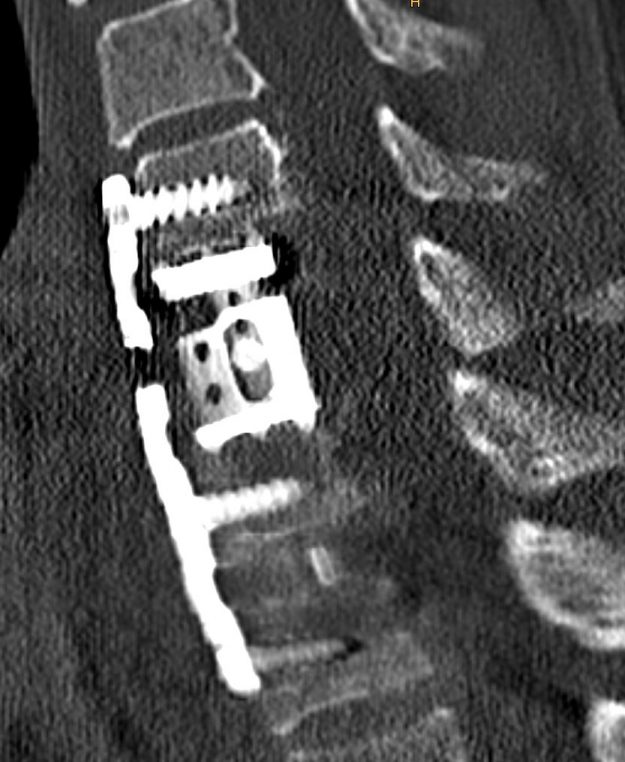

Μετάσταση 10ου Θωρακικού Σπονδύλου (Θ10)

Ασθενής άνδρας 72 ετών με έντονη ραχιαλγία και ιστορικό καρκίνου του πνεύμονα. Ο απεικονιστικός έλεγχος με μαγνητική και αξονική τομογραφία της σπονδυλικής στήλης ανέδειξε μάζα κυρίως στο σώμα του 10ου θωρακικού σπονδύλου (Θ10) με περιβρογχισμό και πίεση επί του νωτιαίου μυελού. (Σημειώστε και τη διήθηση του Θ9 σπονδύλου, χωρίς οστεόλυση). Διενεργήθη αποσυμπίεση του νωτιαίου μυελού…